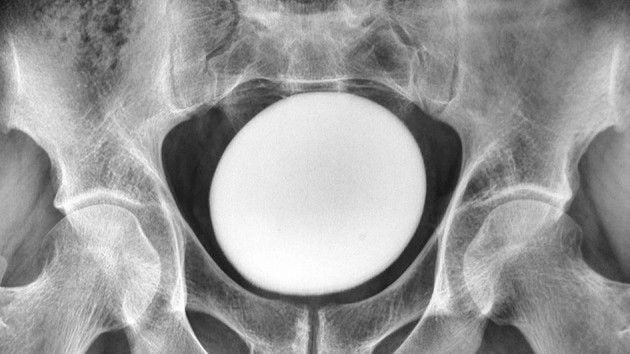

Під час звичайного медичного огляду внизу живота чоловіка лікарі виявили велике тверде утворення. Ультразвукове дослідження виявило гладкий яйцеподібний предмет діаметром 4,3 дюйма (11 сантиметрів). Утворення не було пов’язане з навколишніми тканинами, що полегшувало хірургічне видалення.

Хірурги виконали цистолітотомію — хірургічний розріз сечового міхура — щоб видалити камінь. Через його розмір (приблизно 5 дюймів у довжину, 4 дюйми в ширину та 3 дюйми у висоту) розріз довелося розширити глибше в сечовий міхур.